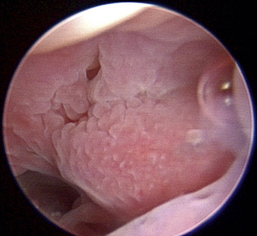

Normal turbinates have a smooth, pink-to-white surface and a spatial alignment that provides channels for the passage of air. The color varies and appears tan in the caudal nasal cavity. Turbinates come in different shapes and sizes, but the surface should be smooth. Ethmoid turbinates in the caudal nasal cavity will have a characteristic stippled or corrugated appearance (Figures 19-13 through 19-16). Ulcerations or various proliferations of the mucosa are indicative of disease. These changes are typically diffuse and accompanied by a lot of mucus. Mucus can be thin to purulent. Copious amounts can be flushed out of the nasal cavity to allow better visibility. The specific disease is determined by biopsy. After full examination of the nasal cavity, run the scope along the floor of the nasal sinus to the level of the choanae. Keeping the scope pointed in a ventral medial direction prevents inadvertent trauma or penetration of the cribriform plate. The index finger of the free hand can be used to follow the scope as it moves caudally over the hard palate; the surgeon can then palpate the scope through the soft palate when it moves into the nasopharynx. Some force is needed to complete this procedure and may result in increased bleeding.

image

Figure 19-13 Normal canine rostral nasal cavity; the septum is medial (left).